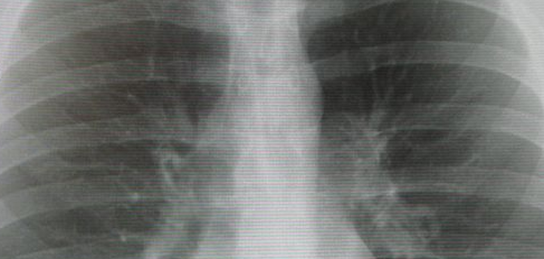

Флюорография грудной клетки – профилактический и диагностический метод рентгенологического обследования органов грудной полости и легких. Флюорография грудной клетки является скрининговым исследованием для выявления рака, туберкулеза и профессиональных болезней легких, - сказала она.

Флюорограмма может быть нормальной — у здорового человека, который раньше не болел никакими заболеваниями легких. Норма флюорографии — это прозрачные легочные поля без каких-либо затемнений.

Бывает флюорограмма патологическая — когда обнаруживаются изменения, свидетельствующие о перенесенной или имеющейся болезни:

Конечно, флюорография легких не даст точнейшую информацию о патологии, но она позволяет своевременно диагностировать изменения в легочных тканях, появление жидкости и клеток новообразований. До сих пор процедура является самой востребованной в профилактической диагностике легких.